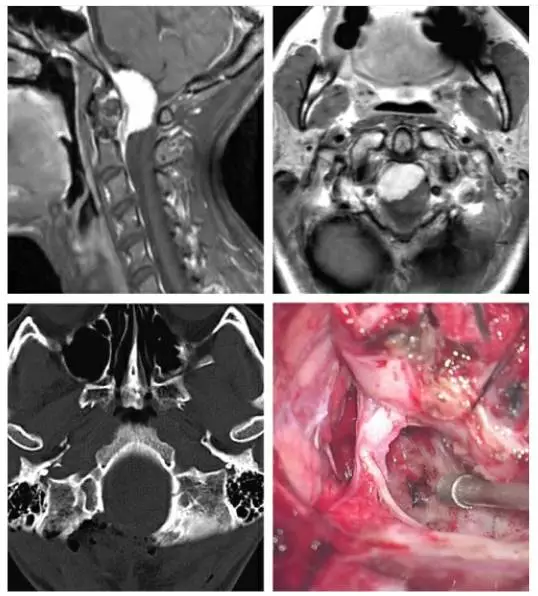

图1. 主体位于枕骨大孔腹侧的脑膜瘤采用如下所述的保守经髁切除(上图)。术后CT扫描显示(左下图)仅切除了足够显露病变的枕髁。椎动脉在穿入硬膜处用缝线牵向外侧。术中图片(右下图)显示至颅颈交界区前方硬膜充分显露和肿瘤切除后的结果。轴外病变通过内减压能够获得足够大的手术空间。

MRI可显示肿瘤的头尾侧范围并指导枕下开颅的大小。另外,病变的腹外侧定位决定枕髁切除的必要程度。脑干及脊髓的水肿、肿瘤的钙化提示软膜侵犯;因为移除肿瘤对软膜无可避免有所骚扰,脑干、脊髓的水肿及肿瘤钙化也和术后神经功能下降的进展相关。对于这样的病例,笔者进行次全切除——在软膜和血管周围留下一薄片肿瘤来保护软膜及穿支血管。包裹血管和肿瘤侵犯进入颈静脉孔(包绕颅神经)也是次全切除的指证之一。

图像评估还应包括CT或常规血管造影来判断肿瘤与毗邻血管(椎动脉,PICA的硬膜外或硬膜下起点)的关系以及椎动脉优势侧。这一信息用于判断同侧椎动脉在PICA起点以近阻断的顺利性。切除高度钙化的肿瘤也是令人生畏的挑战,因其包裹神经血管结构而仅要求行姑息性减压手术。

在这些评估之后,术者依据CT和MRI的详细信息计划枕髁的切除范围。笔者认为枕髁切除在30%以内足以顺利切除全部腹侧病变。通常,到达脑干前方的需的手术通道已经被肿瘤本身拓展变宽,更大范围的枕髁切除就没有必要了。